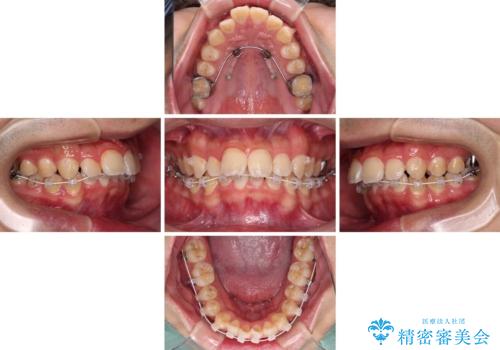

また、左右の犬歯の位置関係は上顎歯列が前方に位置する咬み合わせとなっており、インビザライン単体で治療するよりは、ワイヤー装置や補助装置を併用した方がより良い仕上がりになることが期待されました。

来院時は学生であったので、補助装置により上顎臼歯を後方に移動させ、下顎歯列はワイヤー装置による傾斜を改善させ、就職のタイミングでインビザラインにて仕上げていくこととしました。

インビザラインで難儀する部分をワイヤー装置にて確実に改善しておくことで、インビザラインのみで行うよりも治療期間を短縮するとともに、より理想的な歯列に近づけて仕上げることができました。